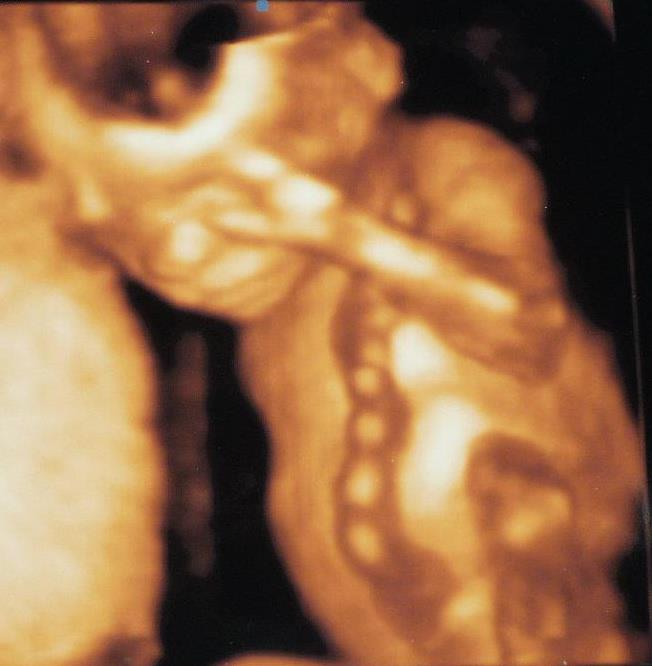

3D fotka z II. screeningu

Ahoj holky, 6.11. jedu na II. screening a chtěla bych 3D fotečku..budu v půlce 20tt, myslíte, že už to půjde? Že na té fotce už půjde něco vidět, poznat nebo je to ještě moc brzo? Děkuji